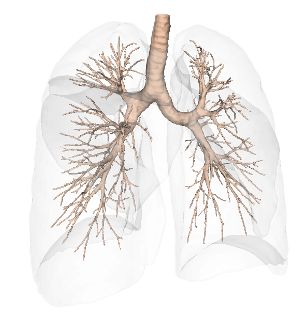

Built on advanced capabilities in lung segmentation and quantification, our AI technology interprets thoracic CT data with anatomical precision - capturing airway trees, parenchymal patterns, and vascular structures, even in severely diseased lungs.

By combining robust Deep Learning methods with tailored software solutions, our technology bridges the gap between imaging and personalized intervention - empowering interventional devices, navigation systems, and robotic platforms.

The modular capabilities can be integrated into early-stage R&D projects and further developed toward regulatory and clinical readiness. LungQ® software modules can be then embedded into interventional systems and clinical workflows to support, advancing personalized procedural planning and intra-operative guidance for high-precision lung interventions, as well as enabling longitudinal post-procedural assessment.